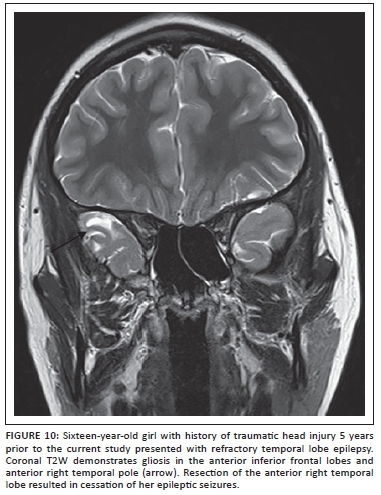

Post-traumatic epilepsy

Seizures and epilepsy are relatively common in children with post-traumatic brain injury (TBI) and portend worse functional outcome.23 The exact pathogenesis of post-traumatic seizures and epilepsy is not well understood, but the window of development of epilepsy after TBI can last up to 10 years or longer after the event.24 It is important to consider post-traumatic epilepsy even in cases where a recent history of trauma is not forthcoming or if the imaging findings seen during a workup for seizures include evidence of trauma such as hemosiderin staining or focal encephalomalacia. Areas of damage that may not be apparent on studies obtained at the time of prior trauma (usually CT scans in the acute period) include the inferior frontal and temporal lobes, which are affected as a result of the contracoup mechanism following trauma over the lateral convexities (Figure 10). Susceptibility-weighted images should be included to increase sensitivity of the study for hemosiderin at sites of prior injury. Post-traumatic seizures may be associated with other pathological changes seen following brain trauma such as reactive gliosis, Wallerian degeneration, microglial scar formation, and cystic white matter lesions. Some of these pathologies have imaging correlates. Studies suggest that post-traumatic seizures may be a result of alterations of intrinsic membrane properties of pyramidal neurons together with enhanced N-methyl-D-aspartate (NMDA) synaptic conductance.23,24